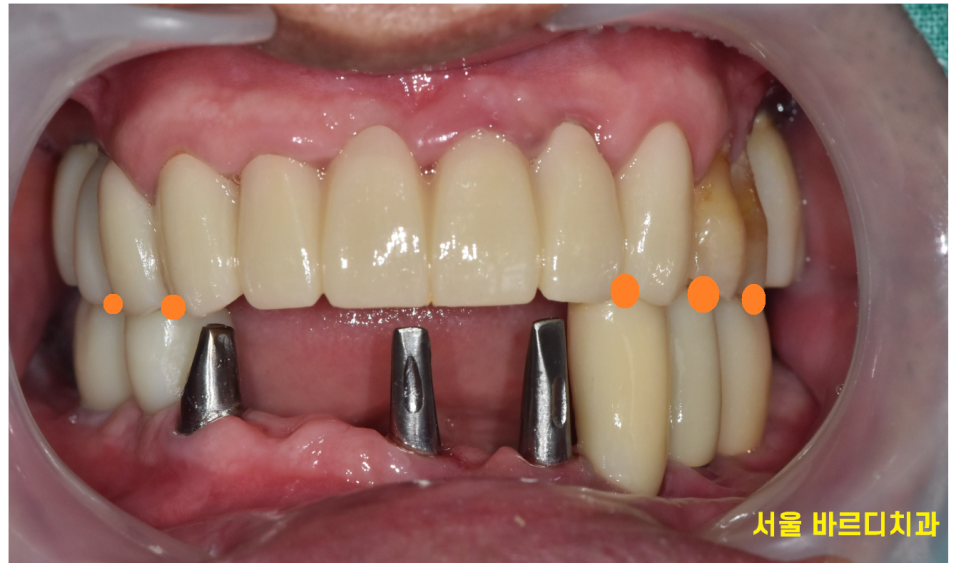

하악 전체 임플란트 치료였기에 높이를 재건해주는게 중요했습니다.

임시치아 과정도 거치고

어금니 부터 제작하여 높이를 복구해준 뒤

아래 앞니 보철을 맨 마지막으로 제작해드렸습니다.

치료 후 사진입니다.

하악 전체 임플란트 7개로 12개의 머리를 완성

상악도 3개의 임플란트 치료를 진행했습니다.